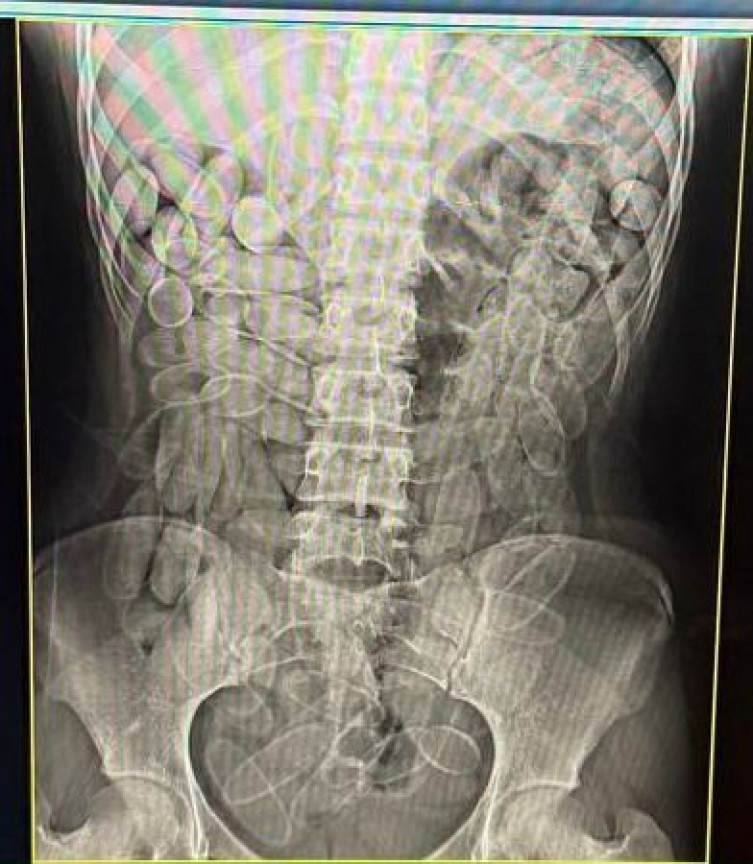

As duas foram encaminhadas ao Pronto-Socorro de Corumbá, onde exames de raio-x confirmaram a presença de cápsulas no organismo. Em seguida, elas confessaram ter ingerido 102 unidades cada uma.